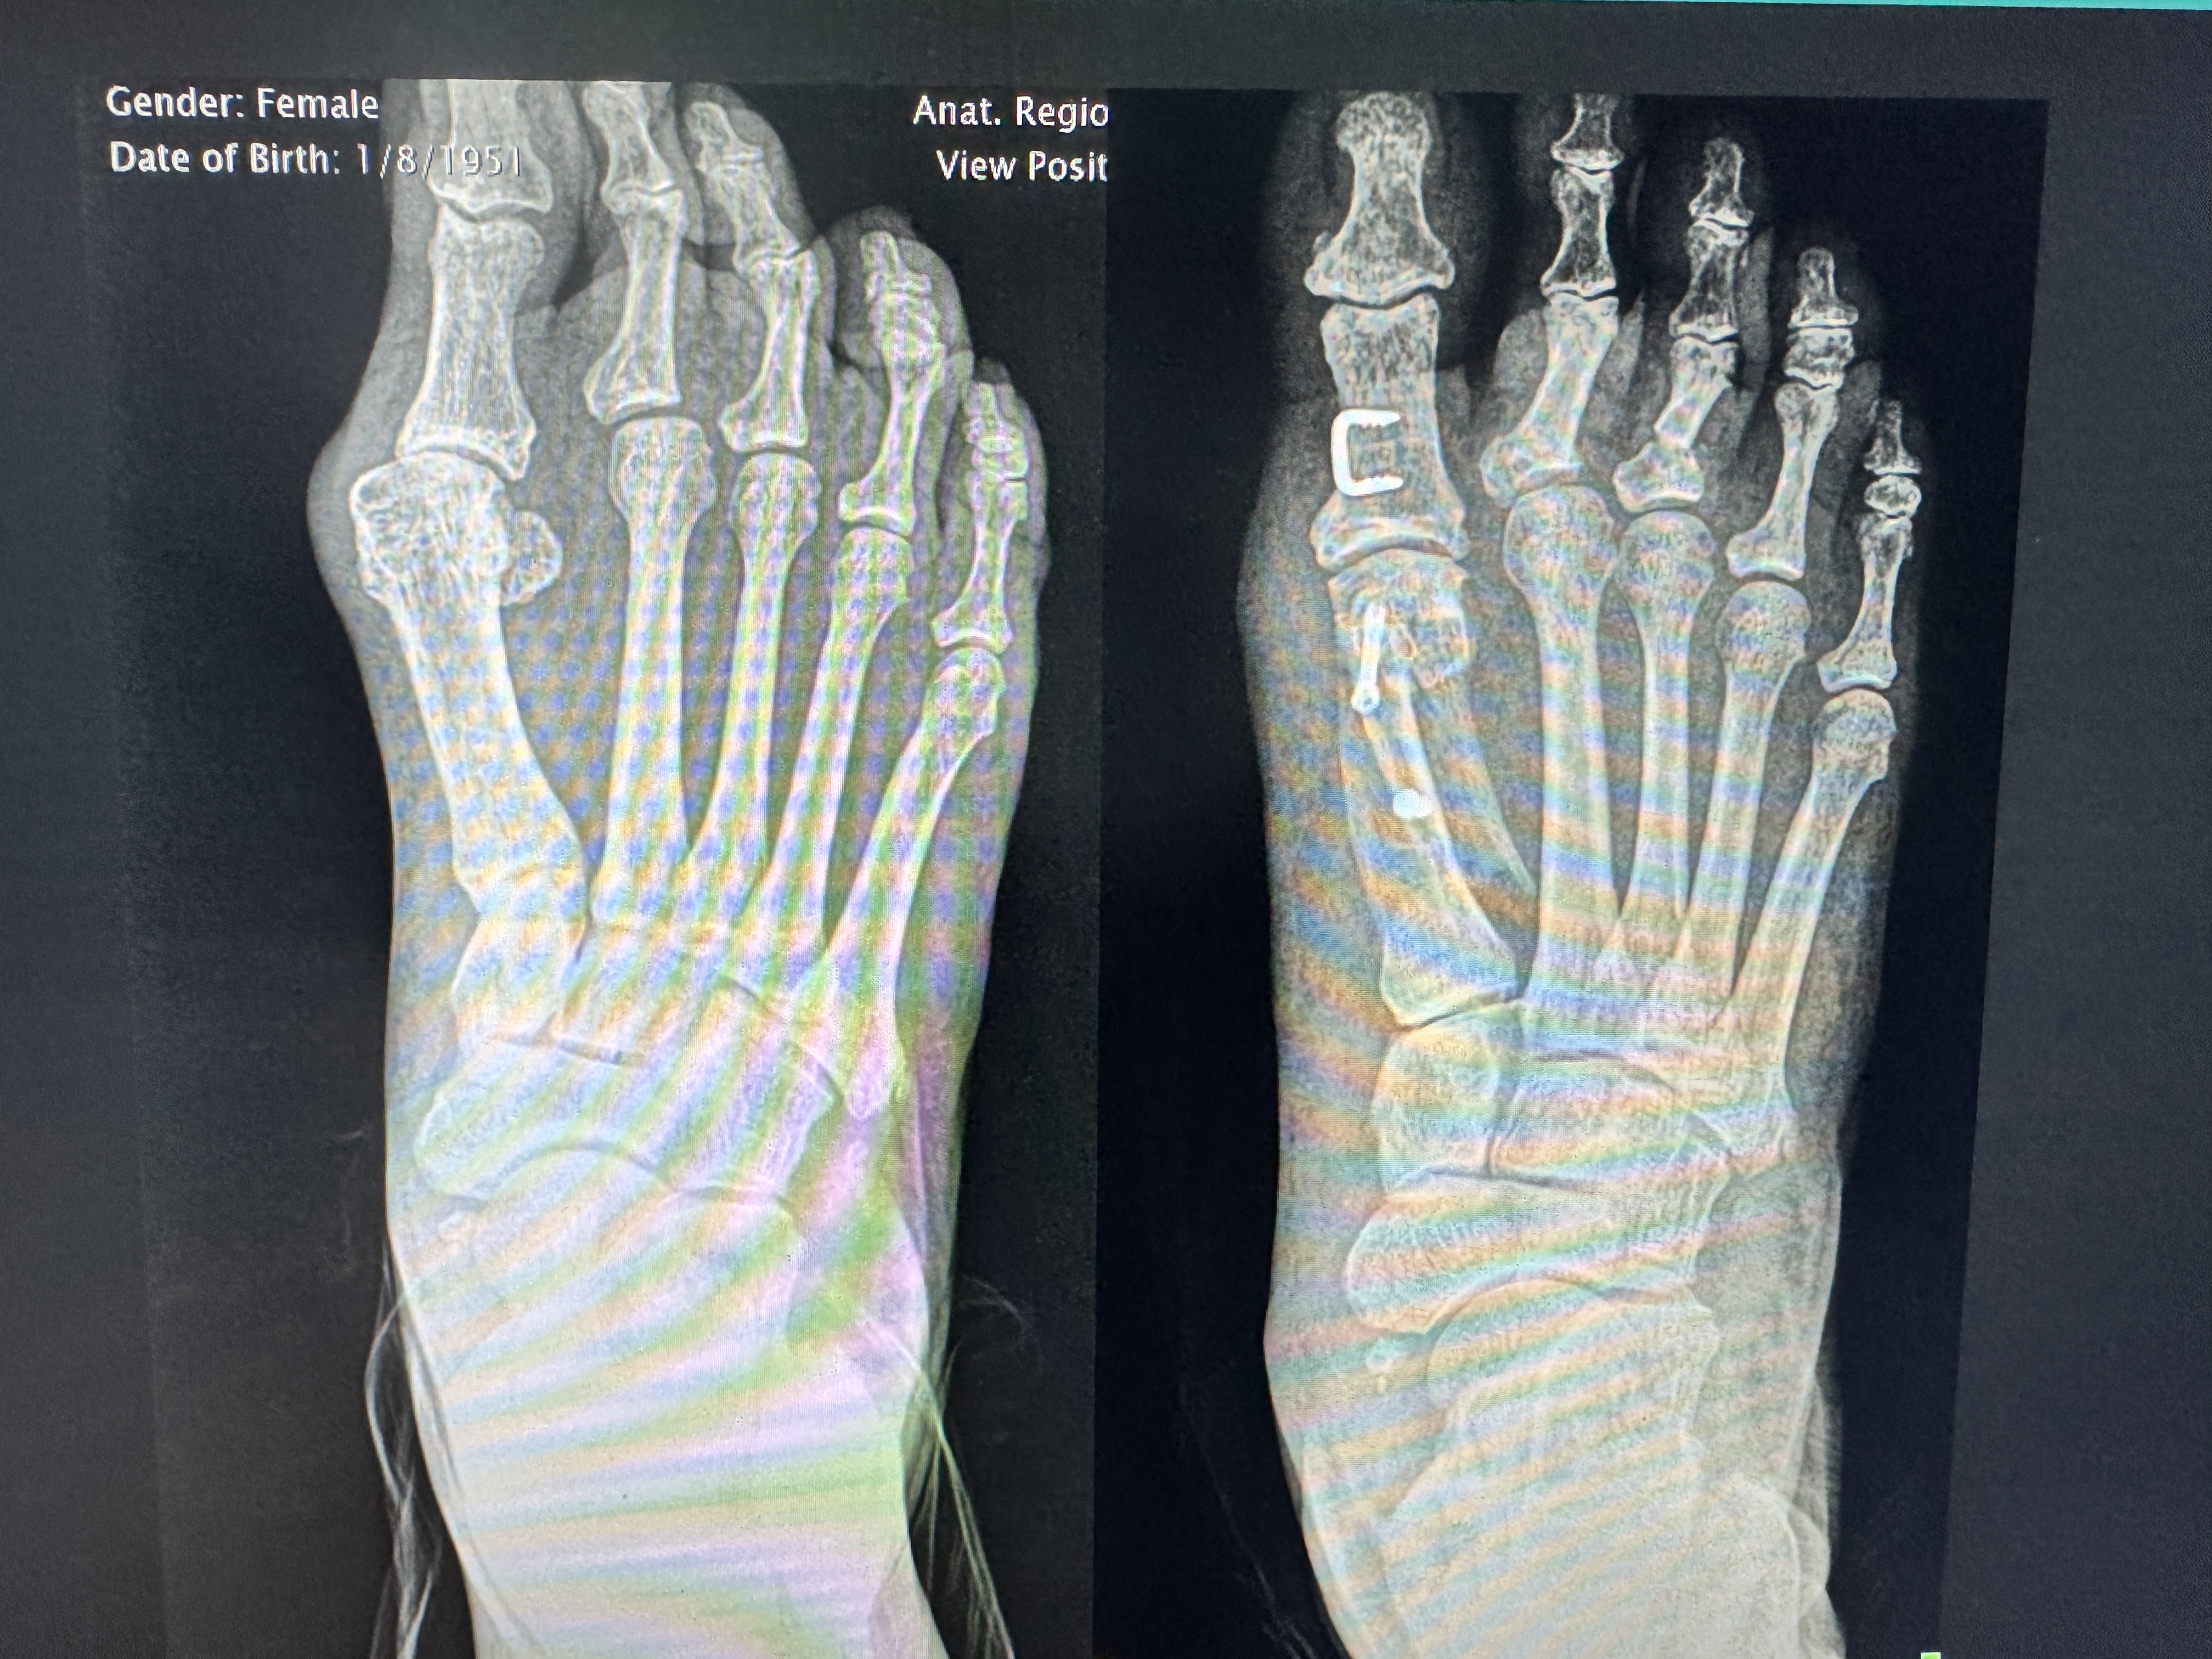

AP weight-bearing X-ray — hallux valgus deformity with metatarsal deviation

Corrected alignment — internal fixation screw visible, first metatarsal realigned

Female patient. Dramatic realignment of the first metatarsal achieved through minimally invasive technique.